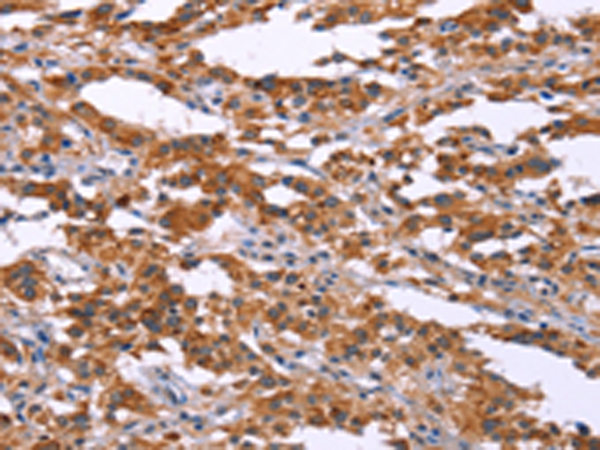

分类: 科研抗体货号: P04248别名: STSL应用: IHC反应种属: Human